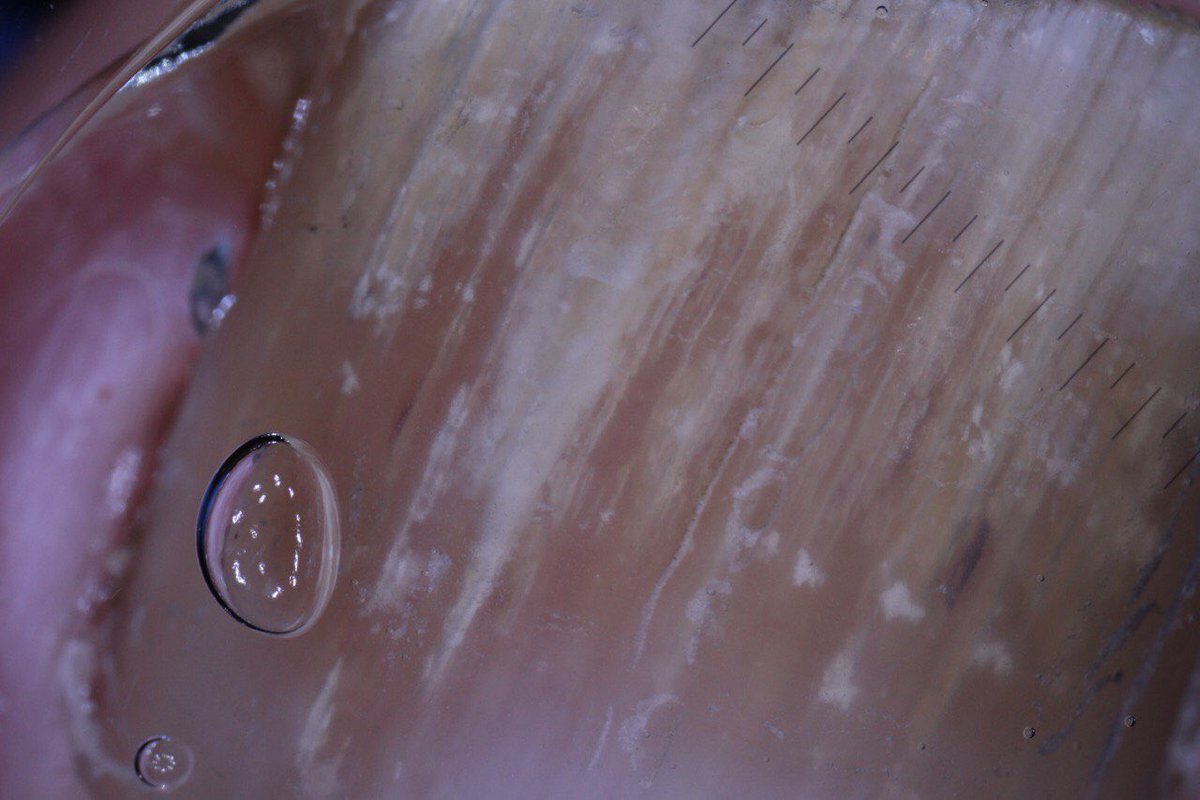

Onicomicosis subungueal distal. Patrón de estrías . Dermatofitos con Clamidiosporas en Ex directo

0

3

10